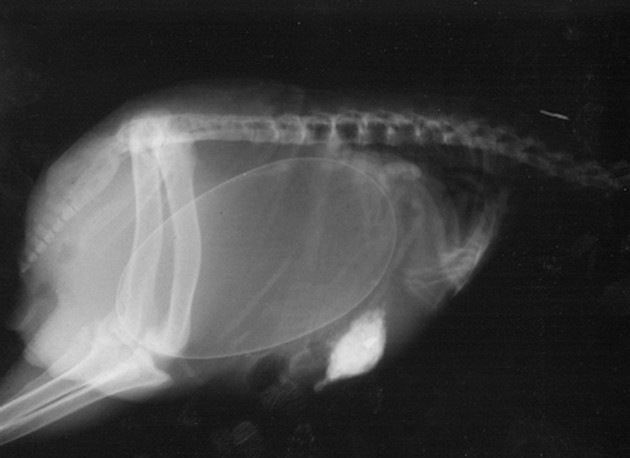

Radostné očakávanie môže u rôznych zvieracích druhov vyzerať všelijako. Fotky, ktoré vám dnes ukážeme sú raritné a rozhodne zaujímavé. Predsa len, videli ste už niekedy tehotné zvieratá cez röntgenové snímky?

Niektoré z nich rodia živé mláďatá, iné zasa kladú vajíčka. Zrod nového života vo zvieracej ríši je každopádne fascinujúci. A ako vyzerajú tehotné zvieratká sa môžete pozrieť na nasledujúcich “lekárskych” snímkoch.

Činčila